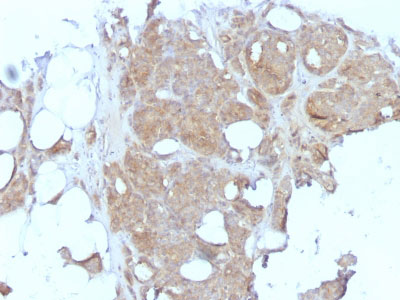

Formalin-fixed, paraffin-embedded human Testicular Carcinoma stained with MVP Monoclonal Antibody (1032).

Formalin-fixed, paraffin-embedded human Breast Carcinoma stained with MVP Monoclonal Antibody (1032). |